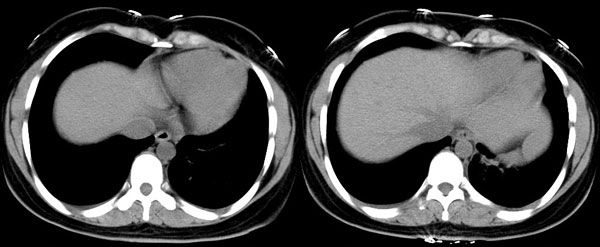

女性,25岁。反复咯血3年,再咯10天。外院x线胸片示:肺炎?支扩?

ct所见:左肺下叶基底段见大片状毛玻璃样改变,其内可见扩张细支气管。

ct诊断:考虑支气管扩张合并感染.

ct所见:左肺下叶基底段见大片状毛玻璃样改变,其内可见扩张细支气管及血管纹理影。后接正常描述。

ct诊断:左肺下叶支气管扩张伴出血。

胸部ct平扫所见:胸廓两侧欠对称,左侧略小,胸壁骨质结构完整。左肺下叶后、外基底段

见大片状毛玻璃样淡薄影,边缘渐淡,其内可见多个环形小囊状影。余肺野清晰,

肺纹理规则,气管支气管通畅,内壁光滑。心脏、大血管大小、形态、密度未见

明显异常,胸膜不厚、光滑,纵隔内未见明显肿大淋巴结。

诊断意见:左肺下叶大片状毛玻璃样淡薄影考虑支气管扩张伴出血。